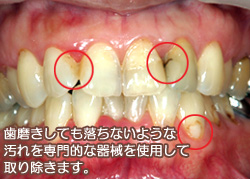

歯にヤニや着色汚れのようなものが付いていませんか? この ヤニ・着色汚れは普段の歯磨きではなかなか落とすことができません 。しかも、主に前歯に付きやすいので気にしている方も多いと思います。.

3歳の子供の前歯が茶色くなってきました。麦茶を飲ませているからでしょうか? 3歳検診の時に簡単に落としてもらったのですが、まだ気になります。 きれいに落とすことはできるのでしょうか? 歯医者さんにはかかったことがないので不安ですが大丈夫でしょうか?. あります!! それは・・・ 今度、紹介します(。・ε・。) ここで症例を一つ(上の前歯の裏から撮影) 3年前に、(写真で右上の)前歯を「 セラミック 」で治療した. 市販品で頑固なヤニを落とすには時間がかかるんです。 「一刻も早くきれいにしたい」そんなあなたには 歯医者に行って自費の「着色汚れを除去する“クリーニング”」 をおすすめします。.

タバコやコーヒーの着色汚れ 歯石 世田谷区千歳船橋駅2分の歯医者 千歳船橋歯科

タバコやコーヒーの着色汚れ 歯石 世田谷区千歳船橋駅2分の歯医者 千歳船橋歯科